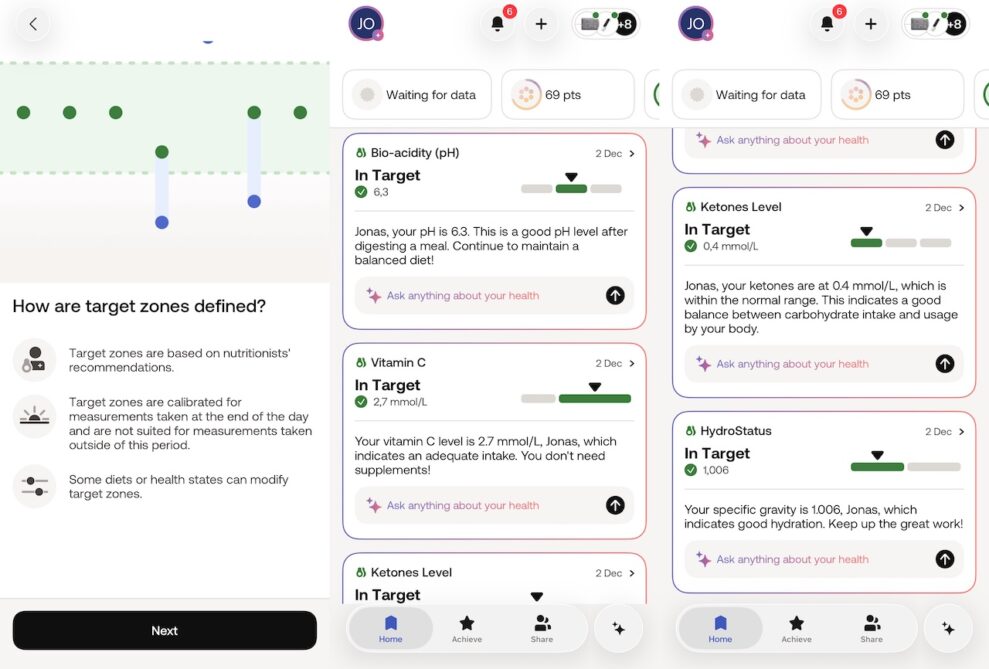

En bra stund efter att man lämnat provet plingar det till i appen och så får man sina resultat. I mitt fall låg PH-värdet inom det normala, om än på gränsen till lågt. Ett lågt värde innebär att man bör se över sin livsstil och vanor. Mina C-vitaminnivåer var optimala så vitamintabletten på morgonen gör tydligen nytta, då jag inte äter mycket citrusfrukter. Ketonmätningen visar normalt, så mitt intag och förbränning av kolhydrater är balanserat. Ett högt värde kunde varit tecken på diabetes, eller för all del en keto-kost. Däremot tyckte appen att jag var lite uttorkad och tyckte att jag borde dricka mer vatten.

Vad abonnemanget på Withings+ tillför är att den inte bara visar värden utan att den försöker hitta förklaringar och ge råd. Jag blev faktiskt lite överraskad av att den som förklaring till uttorkningen föreslog att det kanske kunde bero på den 53 minuters promenad jag hade tagit strax innan mätningen. Inte helt orimligt och jag borde nog ha druckit ett glas vatten när jag kom hem. Man får också tillgång till en AI-tjänst där man kan ställa frågor om sin hälsa och tack vare tillgång till ens hälsodata kan den komma med bättre svar än en AI-chatbot på nätet. Speciellt om man delar alla sina data med appen.